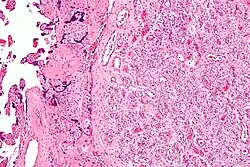

Micrograph of a chorangioma. H&E stain.